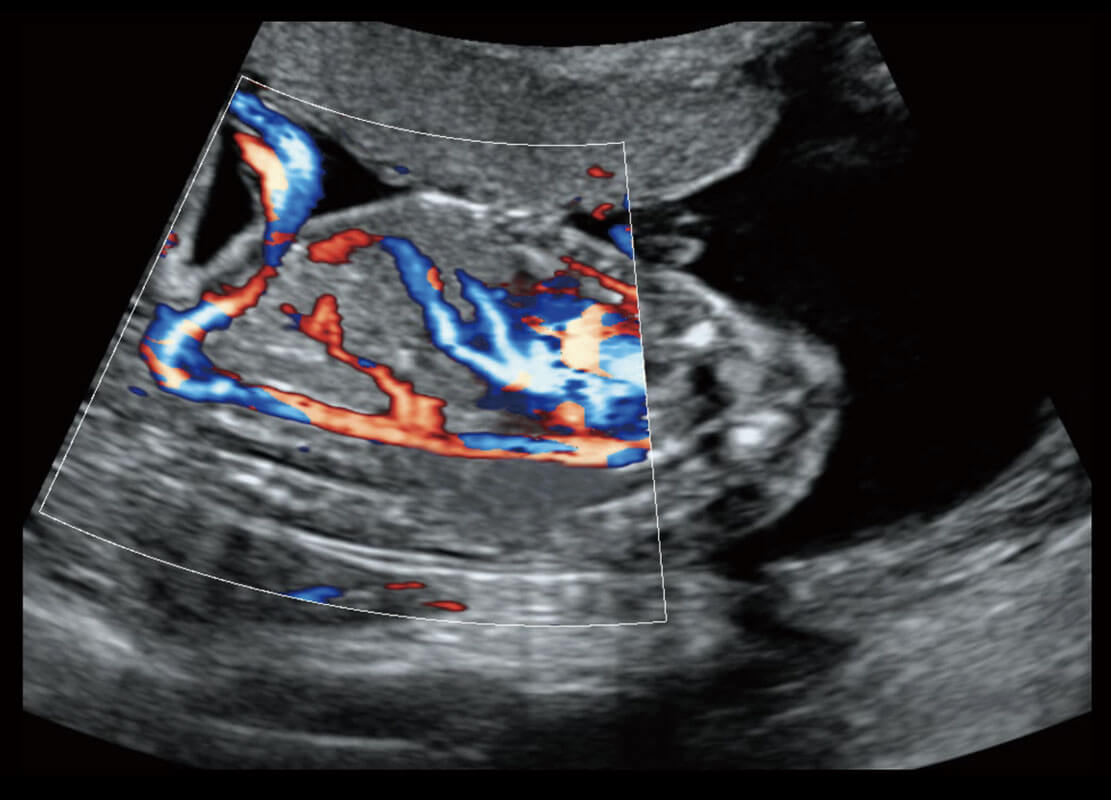

P60搭载一系列胎儿心脏成像技术,实现精细的胎儿心脏评估。

四腔心血流